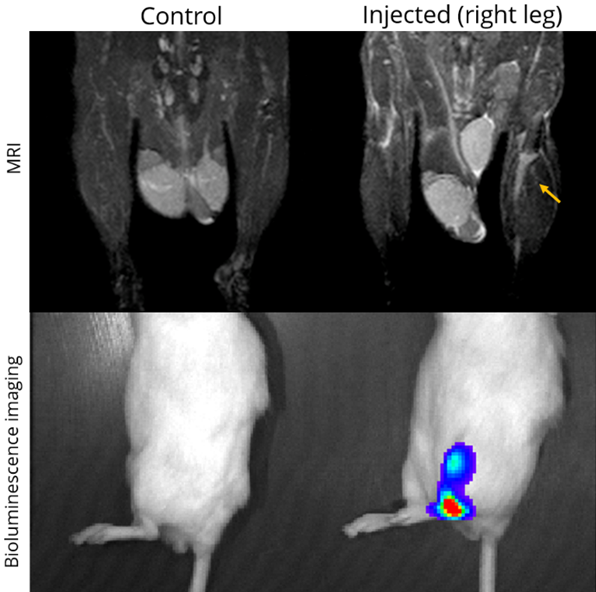

MRI is a complementary method to bioluminescence imaging in the detection of tumors, allowing a more precise assessment of the location and extent of orthotopic tumors (here, an orthotopic model of prostate bone marrow metastasis). Image Credit: Scintica Instrumentation Inc